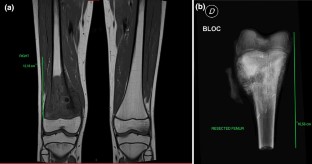

Fig. 1

Fig. 2

Fig. 3

Fig. 4

Fig. 5